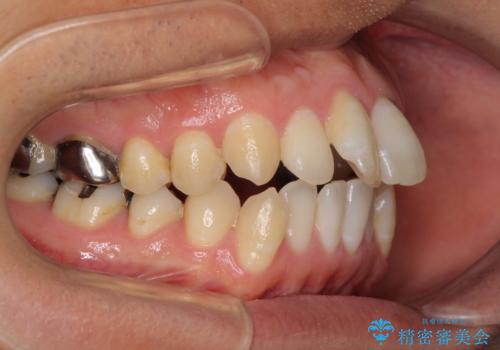

通常の咬み合わせ位置と比較して、上顎の歯列が全体的に前方にある状態で、上下前歯の前後方向の位置に著しい差がありました。

上顎奥歯付近にアンカースクリューを用い、上顎歯列全体の後方移動と、大臼歯圧下を促し、前歯の上下関係を改善することとしました。

奥歯には目立つ銀歯が多くあるので、矯正治療後には下顎の銀歯をセラミッククラウンやセラミックインレーにより、補綴・修復治療することとしました。